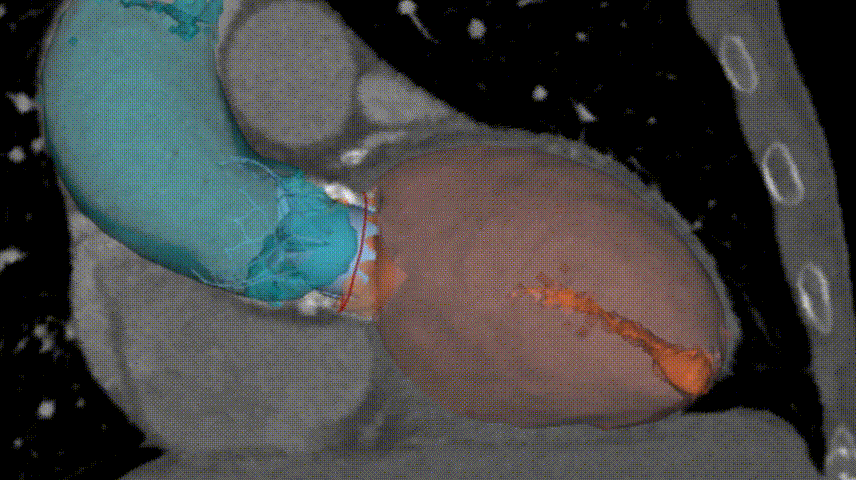

应用基于人工智能技术的术前分析辅助决策软件进行术前评估

通过术前测量,对病例深入分析,结合人工智能术前分析辅助决策软件进行三维和二维图像融合,安贞医院心外科瓣膜中心王坚刚主任王盛宇主任郑帅医师孟斐医师胡秋明医师李岳环医师沈经纶医师吴凯胜医师等团队多次讨论,并经过侯晓彤副院长朱俊明主任等医院心外科质量委员会专家集体讨论,认为本例手术不管是进行外科生物瓣置换还是行经导管瓣膜置换术,均存在极高的手术风险。主要包括:

5.经由心尖入路采取0位释放的方式,植入Xcor-26经导管主动脉瓣膜系统瓣膜,完成TAVR手术治疗。